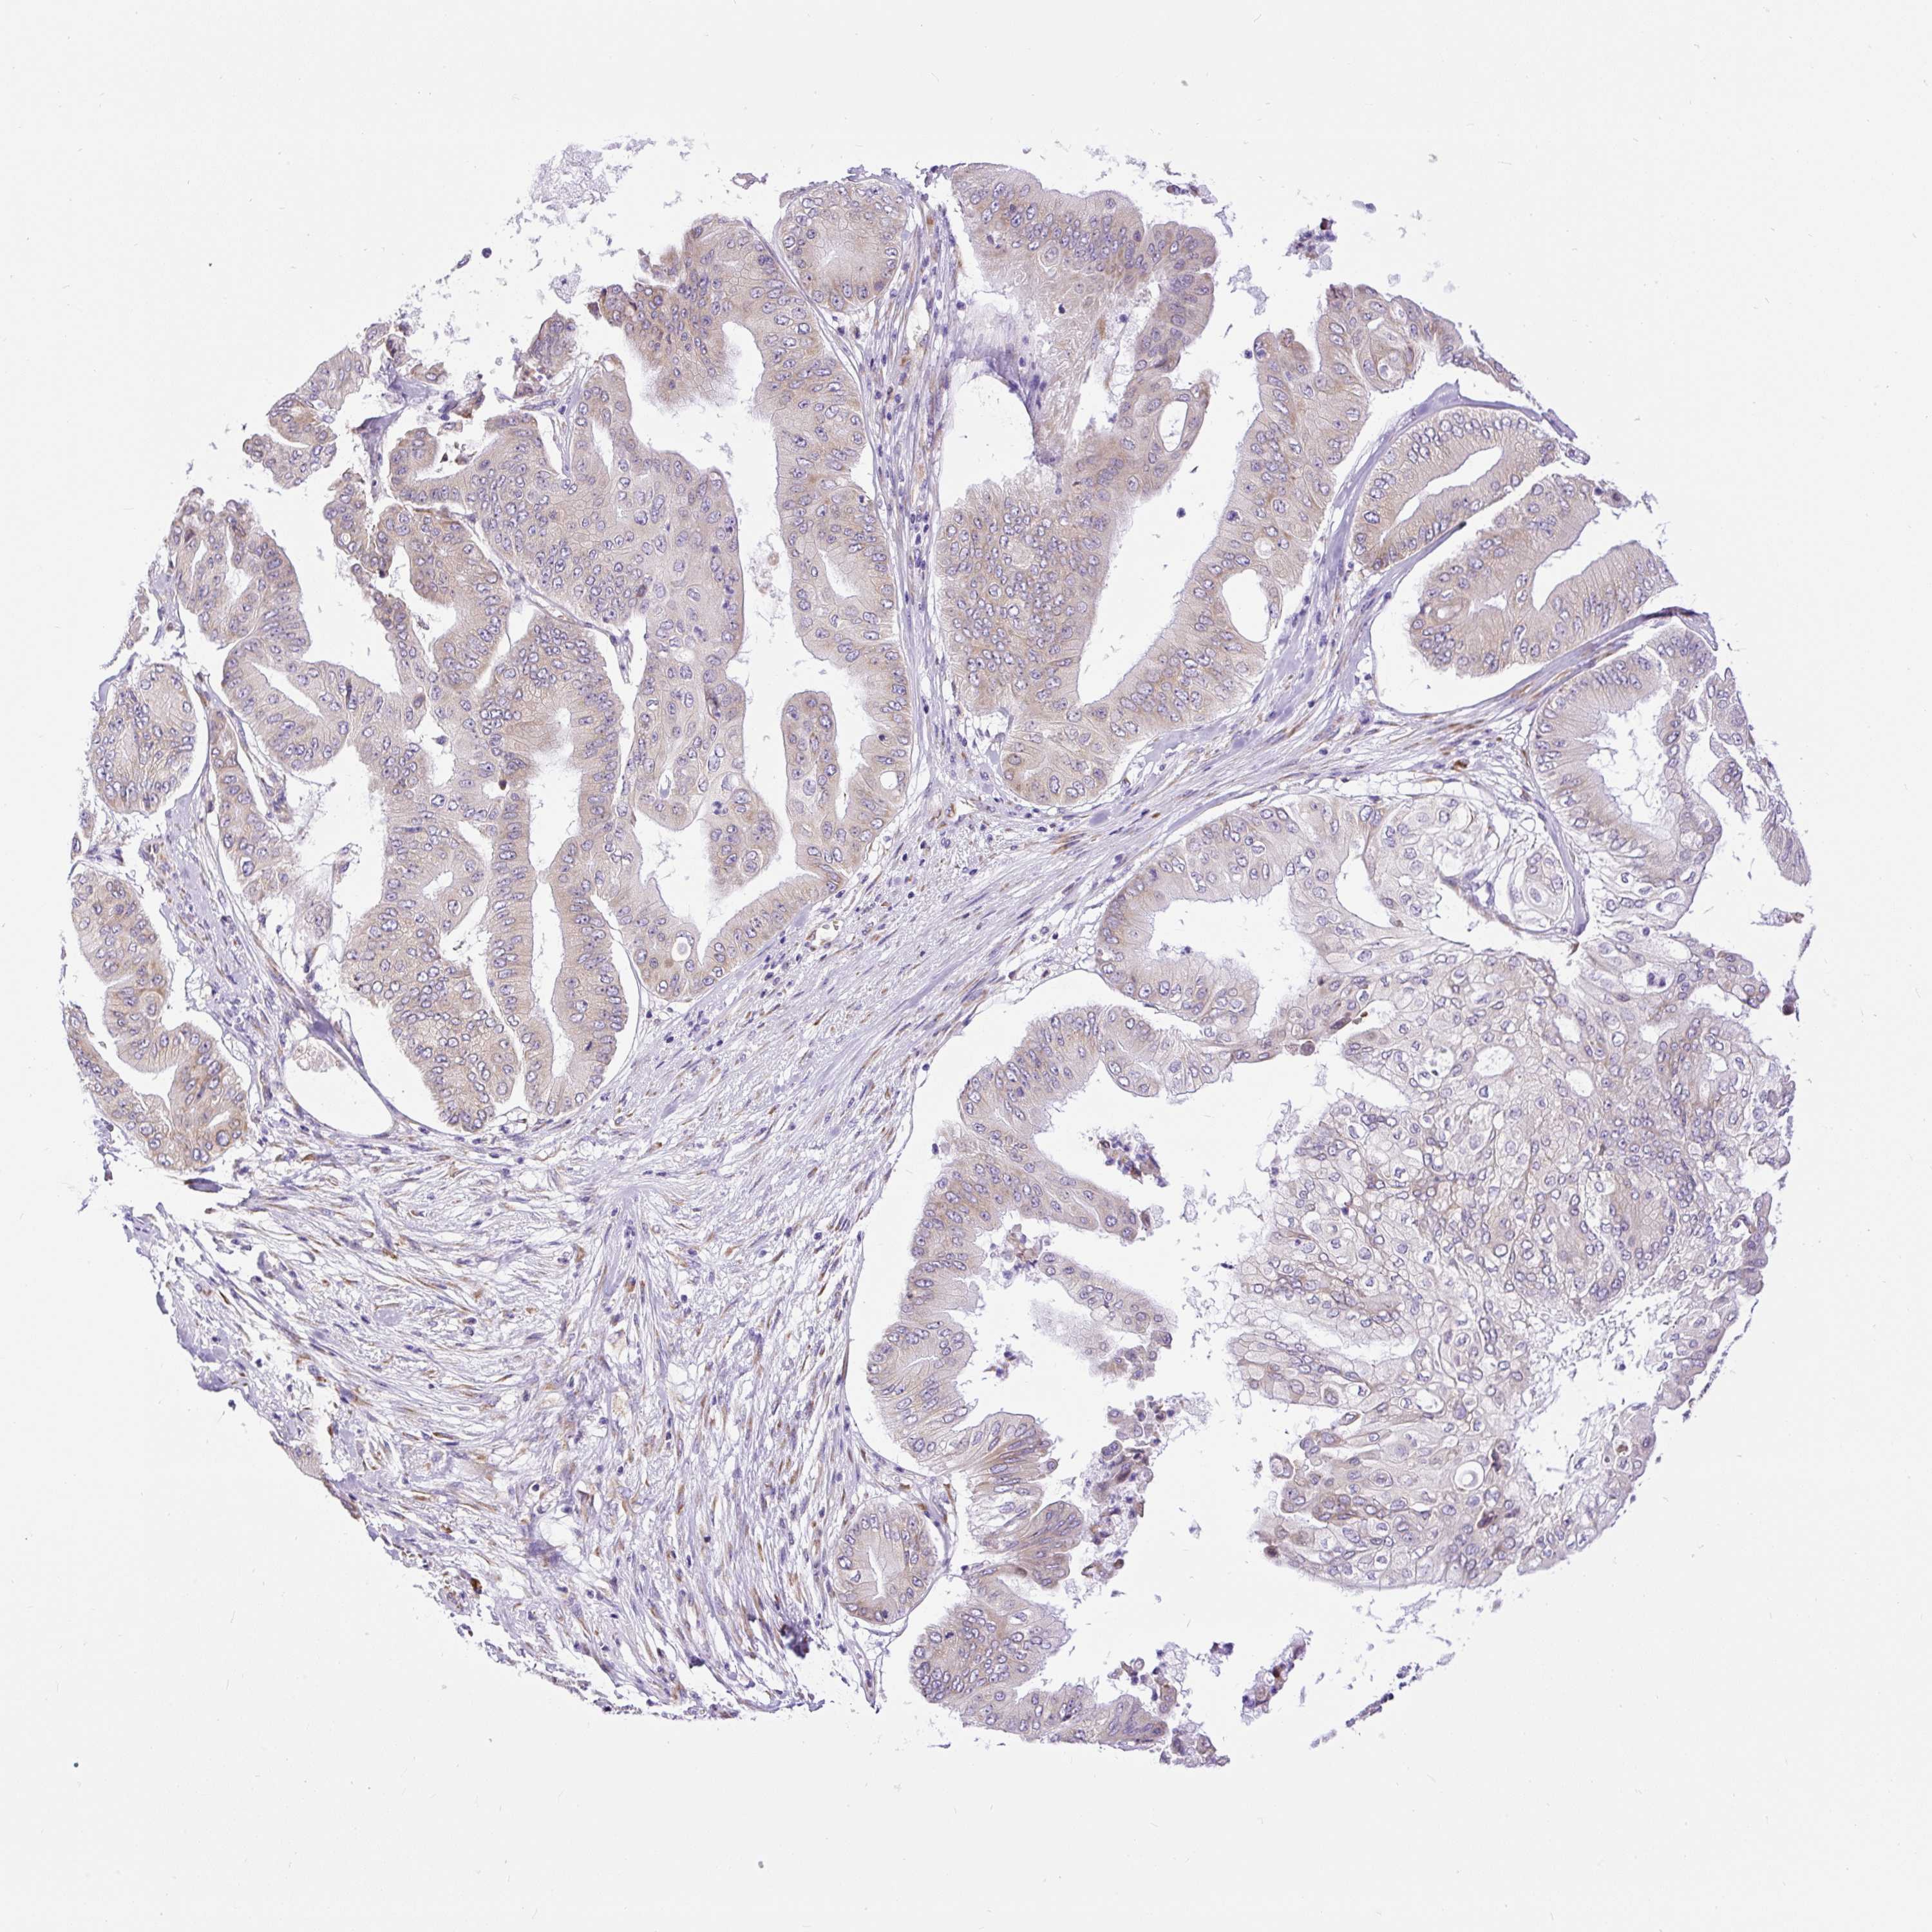

PANCREATIC CANCER - Protein expressioni

A mouse-over function shows sample information and annotation data. Click on an image to view it in a full screen mode. Samples can be filtered based on level of antibody staining by selecting one or several of the following categories: high, medium, low and not detected. The assay and annotation is described here.

Note that samples used for immunohistochemistry by the Human Protein Atlas do not correspond to samples in the TCGA dataset.

Antibody stainingi

Antibody staining in the annotated cell types in the current human tissue is reported as not detected, low, medium, or high, based on conventional immunohistochemistry profiling in selected tissues. This score is based on the combination of the staining intensity and fraction of stained cells.

Each image is clickable and will lead to virtual microscopy that enables deeper exploration of all samples and also displays staining intensity scores, fraction scores and subcellular localization as well as patient and tissue information for each sample.

Antibody HPA046841

Antibody HPA052867

Antibody CAB009746

Staining

High

Medium

Low

Not detected

Intensity

Strong

Moderate

Weak

Negative

Quantity

>75%

75%-25%

<25%

None

Location

Nuclear

Cytoplasmic/membranous

Cytoplasmic/membranous,nuclear

Adenocarcinoma, NOS

Adenocarcinoma, metastatic, NOS